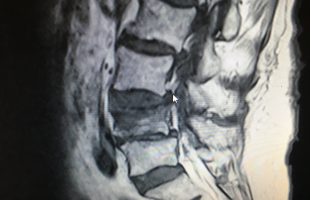

Η Ρομποτική Χειρουργική ενισχυόμενη από την Τεχνητή Νοημοσύνη αποτελεί μεγάλη εξέλιξη στη θεραπευτική αγωγή. Ο συνδυασμός αυτών συμβάλει ουσιαστικά: α. Στον προεγχειρητικό σχεδιασμό β. Στην επιτέλεση της χειρουργικής πράξης με την μέγιστη δυνατή ακρίβεια γ. Στη μείωση των επιπλοκών δ. Στην μείωση του χειρουργικού χρόνου ε. Στον ουσιαστικό περιορισμό της προσλαμβανόμενης ακτινοβολίας από το προσωπικό